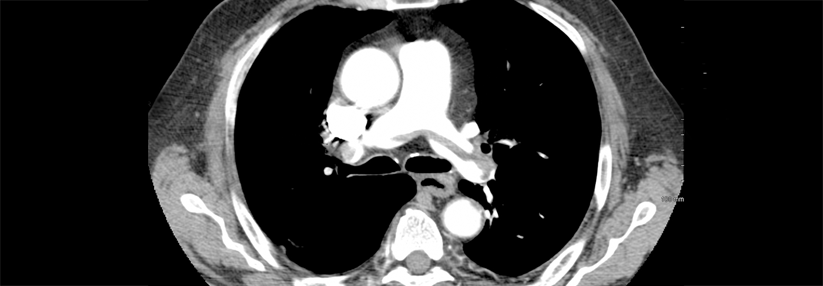

Tumorpatienten weisen ein erhöhtes Risiko für die Entstehung von Thromboembolien auf.

Eine primäre Thromboseprophylaxe wird zwar empfohlen, doch scheint sie bei Krebspatienten, die in ambulanten Settings systemische Tumortherapien erhalten, nicht optimal umgesetzt zu werden. Dr. Marliese Alexander vom Peter MacCallum Cancer Centre in Melbourne und Kollegen untersuchten, ob die Rate an Thromboembolien verringert werden kann, wenn die Thromboseprophylaxe auf Basis einer biomarkergestützten Risikoeinschätzung erfolgt.

Patienten mit Lungen- oder gastrointestinalen Tumoren (n = 328), die mit einer systemischen Tumortherapie begannen, wurden in die offene Phase-3-Studie TARGET-TP aufgenommen. Entsprechend ihrer Fibrinogen- und D-Dimer-Werte teilte man die Patienten in zwei Gruppen…